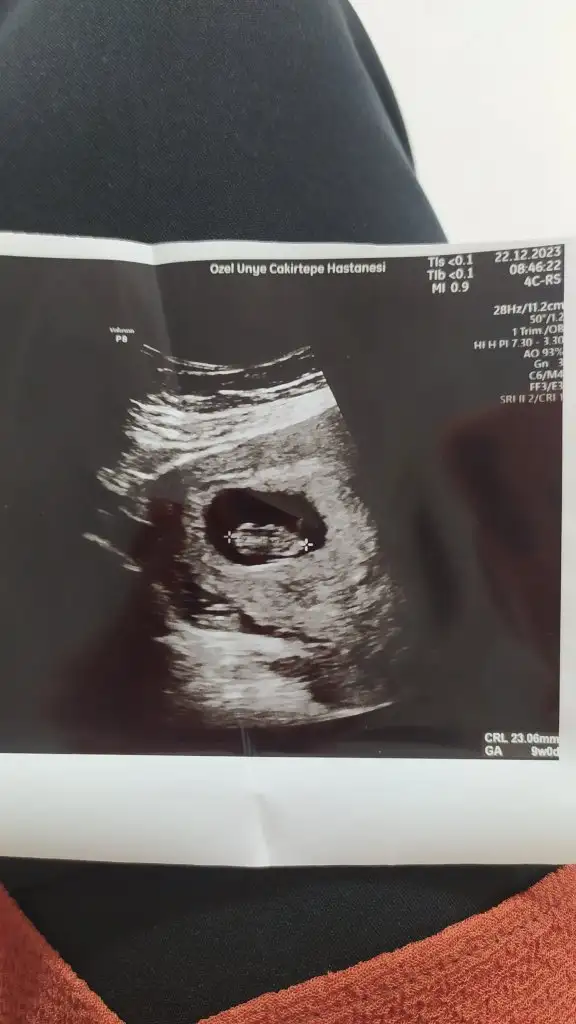

Benimkinede bakarmısınız rica etsem 9+5Selam Kızlarbir çok kişi gruplardan beni bilir. Yine yetiştim imdatlara

5 ve 14. haftaya kadar olan ultrason fotolarınızı paylaşın. Vajinadan mı yoksa karından mı çekildiğini ve kaç haftalık olduğunu da mutlaka belirtin.